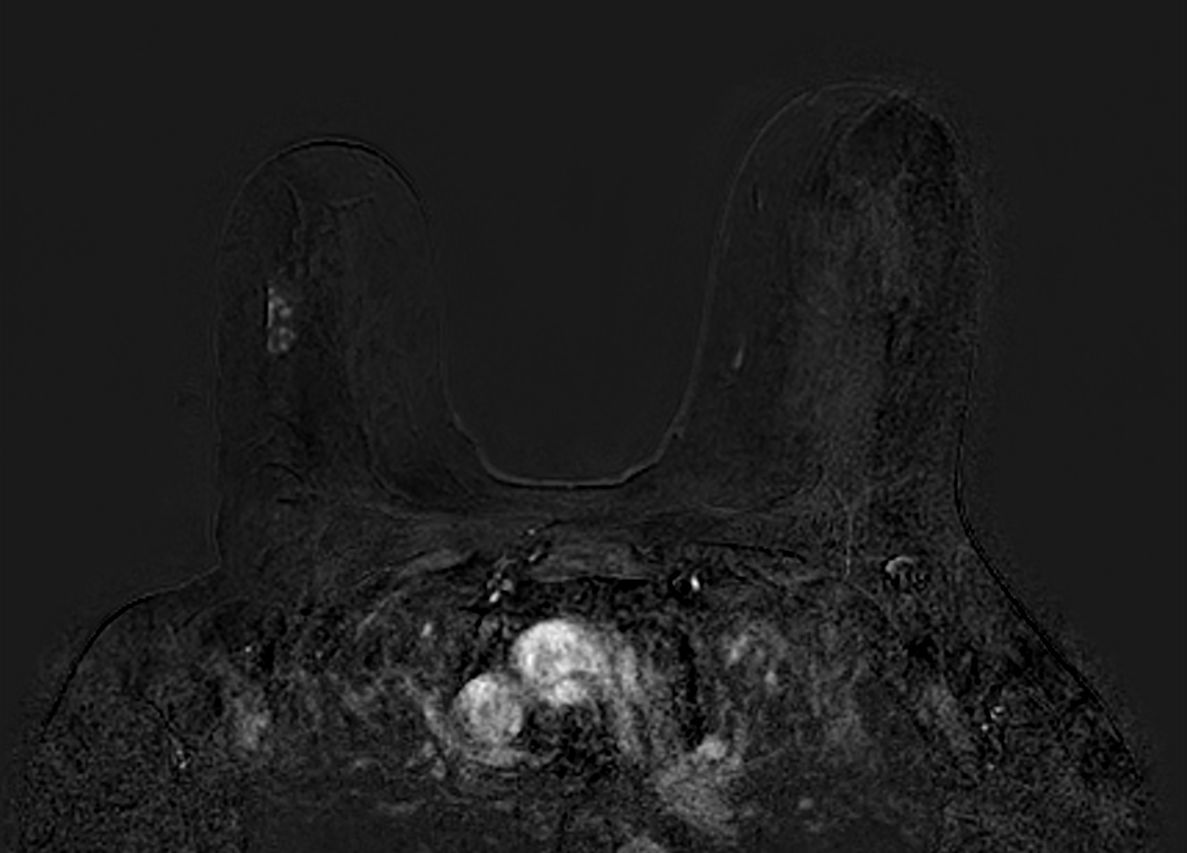

Axial 3D T1w FFE - Subtraction